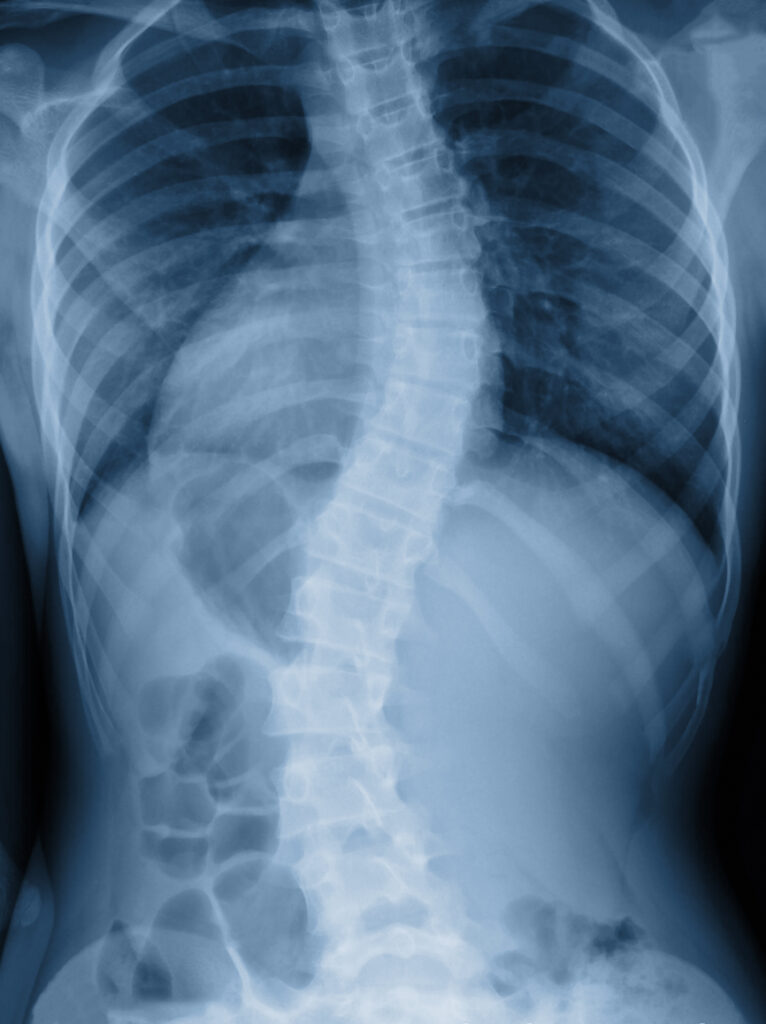

Scoliosis is a condition where the spine curves sideways, often in an “S” or “C” shape. While mild cases may cause little disruption, more severe scoliosis can lead to:

scoliosis and social security disability

• X-rays or MRI scans showing spinal curvature